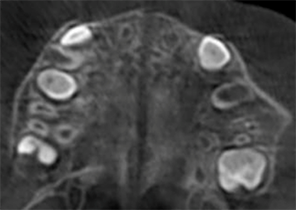

Case Report 1

10 years 0 months old, 18 stages of Invisalign Palatal Expanders

Courtesy of Dr. Sandra Khong Tai

Pre Invisalign Palatal Expander Expansion

Post Invisalign Palatal Expander Expansion

After Invisalign First treatment